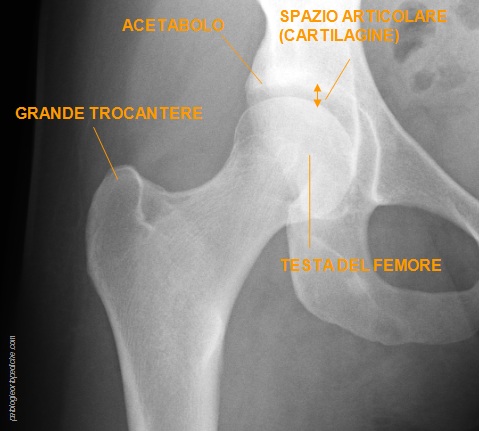

rx-anca